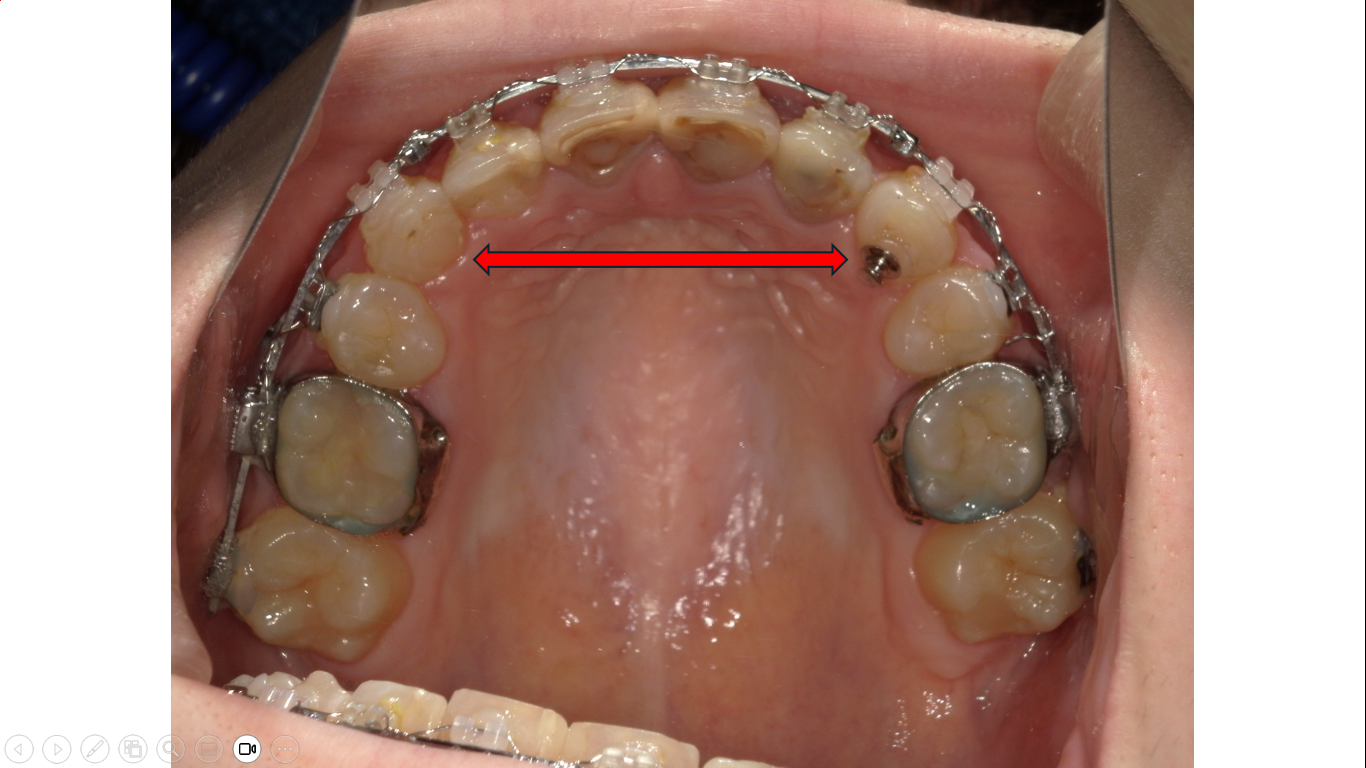

上の写真は左右犬歯間の幅径が大きくなったことが分かります。

上の写真は口蓋側からの歯列全体の遠心移動を行っているところです。この様な装置に替えることで犬歯間の幅径を縮小できました。

動的治療終了時の咬合面観です。広がっていた上顎左右犬歯間の幅径が狭く適正な幅になりました。